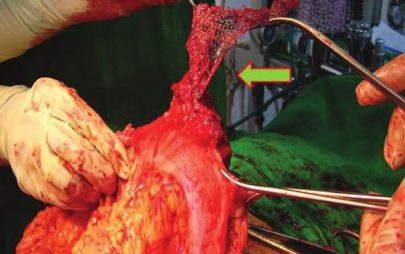

Przyczyną nieznośnego bólu może być złe umocowanie siatki – np. użycie nie wchłaniających się zszywek. Obok zdjęcia z usuwania siatki z mocowanej metalowymi zszywkami, które (co oczywiste) bolały chorego. Ból, uczucie stałej przeszkody był nie do wytrzymania. W czasie operacji okazało się, że metalowych zszywek jest bardzo dużo, były ostre, kłuły. Sama siatka była sztywna i niedopasowana do ciała młodego człowieka. Jedynym rozwiązaniem było usunięcie siatki z zszywkami.

Usuwanie siatki to zwykle rozległa operacja i ciało jest okaleczone. Po usunięciu siatki może powstać nawrót przepukliny. Nie wykluczone, że chorego czeka kolejna operacja; na siatkę już się nie zdecyduje.